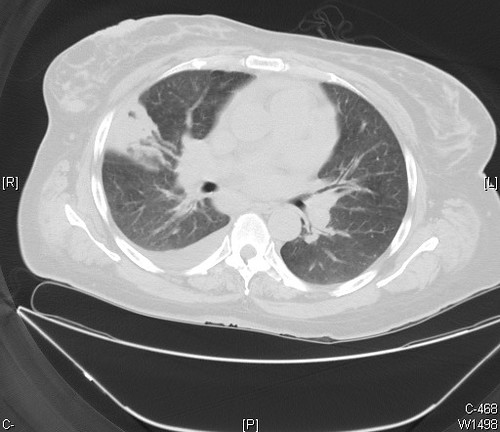

- The infarct in this Ct scan is represented by the wedge shaped density in the right lung with its base abutting the pleura. (“Pulmonary infarction, right lung Case 209” by Pulmonary Pathology is licensed under CC BY-SA 2.0)